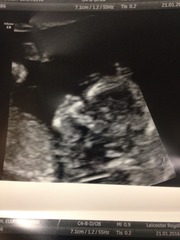

Scan went well, I got a huge wave of relief when I saw the heartbeat! Baby was tucked right down and wouldn't play ball at all, I had to wiggle around, go for a walk etc before she could get any measurements and even then it took a while! We saw baby kicking and moving, opening & closing its mouth, even saw its tiny hands and feet - ten teeny toes already all present and correct, just amazing. Dates were exactly in line with mine, 12+6 today, giving me a due date of 29th July. I feel so ridiculously lucky Grin

yey coco !!! Amazing scan, so happy for you. Such a cute bub! Grin

I actually had tears in my eyes four, seeing your scans. Hormones! Can't imagine what will happen when I see mine Blush

Congrats GlenCo! Lovely pics!

Hi everyone, new thread time already! Lovely scan pictures Four